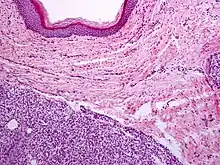

Capillary hemangioma

Strawberry naevus, H&E stain

A precise history of the growth characteristics of the IH can be very helpful in making the diagnosis. In the first 4 to 8 weeks of life, IHs grow rapidly with primarily volumetric rather than radial growth. This is usually followed by a period of slower growth that can last 6–9 months, with 80% of the growth completed by 3 months. Finally, IHs involute over a period of years.[34] The exceptions to these growth characteristics include minimally proliferative His, which do not substantially proliferate[33] and large, deep IHs in which noticeable growth starts later and lasts longer.[34] If the diagnosis is not clear based on physical examination and growth history (most often in deep hemangiomas with little cutaneous involvement), then either imaging or histopathology can help confirm the diagnosis.[31][35] On Doppler ultrasound, an IH in the proliferative phase appears as a high-flow, soft-tissue mass usually without direct arteriovenous shunting. On MRI, IHs show a well-circumscribed lesion with intermediate and increased signal intensity on T1- and T2-weighted sequences, respectively, and strong enhancement after gadolinium injections, with fast-flow vessels.[31] Tissue for diagnosis can be obtained via fine-needle aspiration, skin biopsy, or excisional biopsy.[36] Under the microscope, IHs are unencapsulated aggregates of closely packed, thin-walled capillaries, usually with endothelial lining. Blood-filled vessels are separated by scant connective tissue. Their lumina may be thrombosed and organized. Hemosiderin pigment deposition due to vessel rupture may be observed.[37] The GLUT-1 histochemical marker can be helpful in distinguishing IHs from other items on the differential diagnosis, such as vascular malformations.[32]